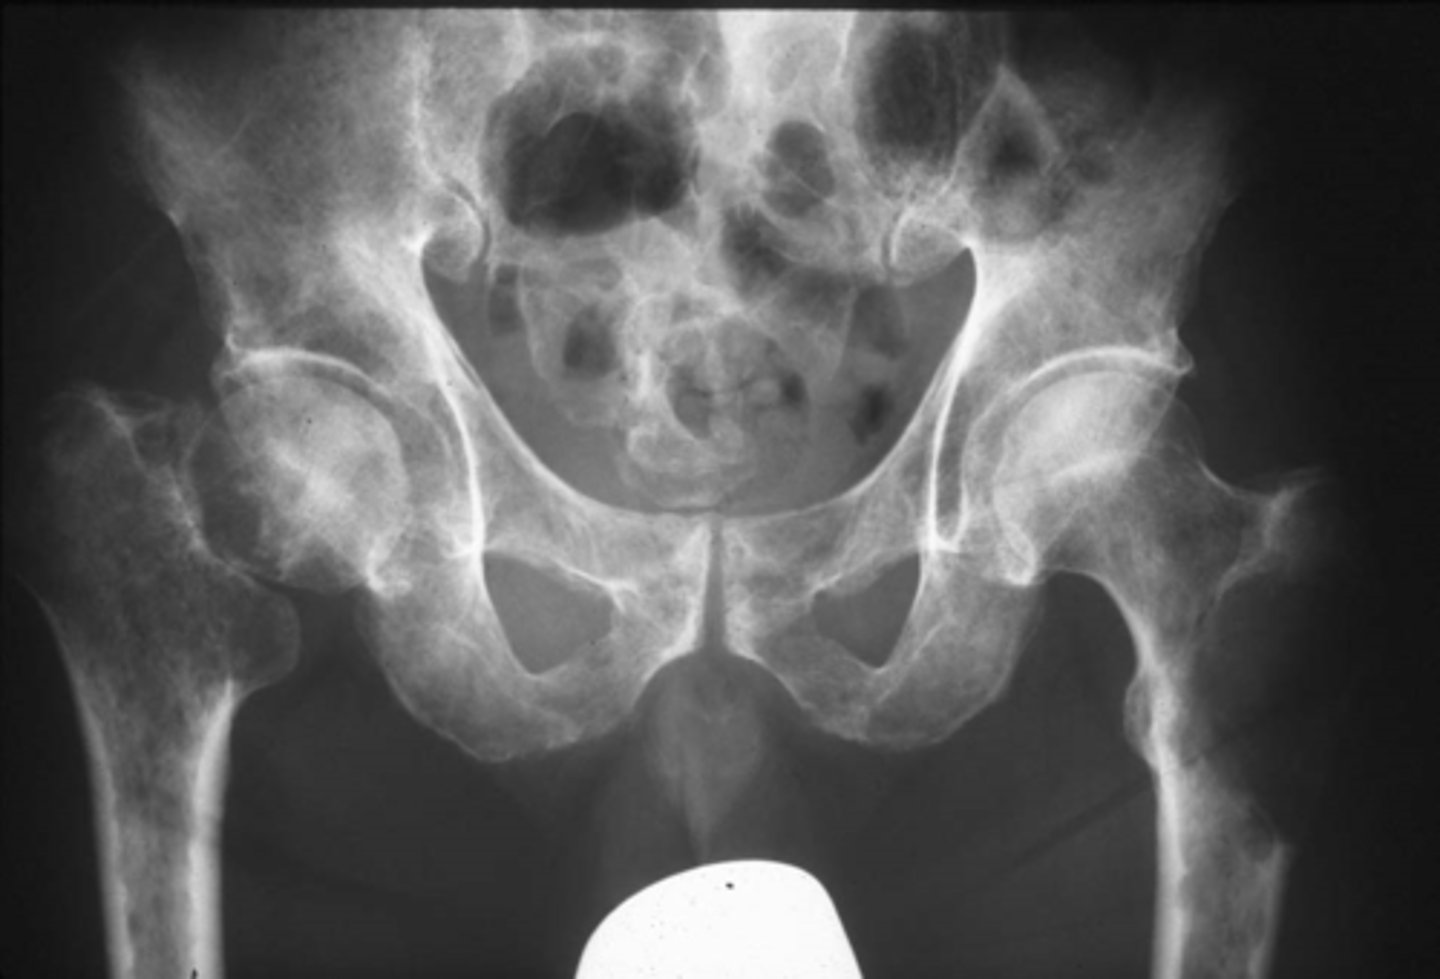

Vignette # 5

Sex: Male

Age: 50

Chief Complaint: Patient presents with hip pain that’s a 6 out of 10 on the pain scale. Objective Findings: Hibbs+, Anvil+

Diagnostic imaging: X-ray

1. List the radiographic signs that you are expecting to see. (Choose 3)

a. Ground glass

b. Osteolytic lesion

c. Joint destruction

d. Osteopenia

e. Metaphyseal Lesion

f. Expansile lesion

g. Cortical thickening

h. Sclerosis

Primary neoplasm

Hematopoetic disease

Multiple myeloma

2. What is the most likely diagnosis? (Choose 3)

a. GCT

b. Blastic lesion

c. Primary neoplasm

d. Paget’s disease

e. Fibrous dysplasia

f. Hematopoetic disease

g. Blastic metastasis

h. Multiple myeloma

3. List the possible future sequelae of this condition. (Choose 3)

a. Anemia

b. Prostate cancer

c. Urinary incontinence

d. Increase in occurrence of infection

e. Unexplained weight loss

f. Skin deformities

g. Increase in PSA

h. Increase in acid phosphate enzyme